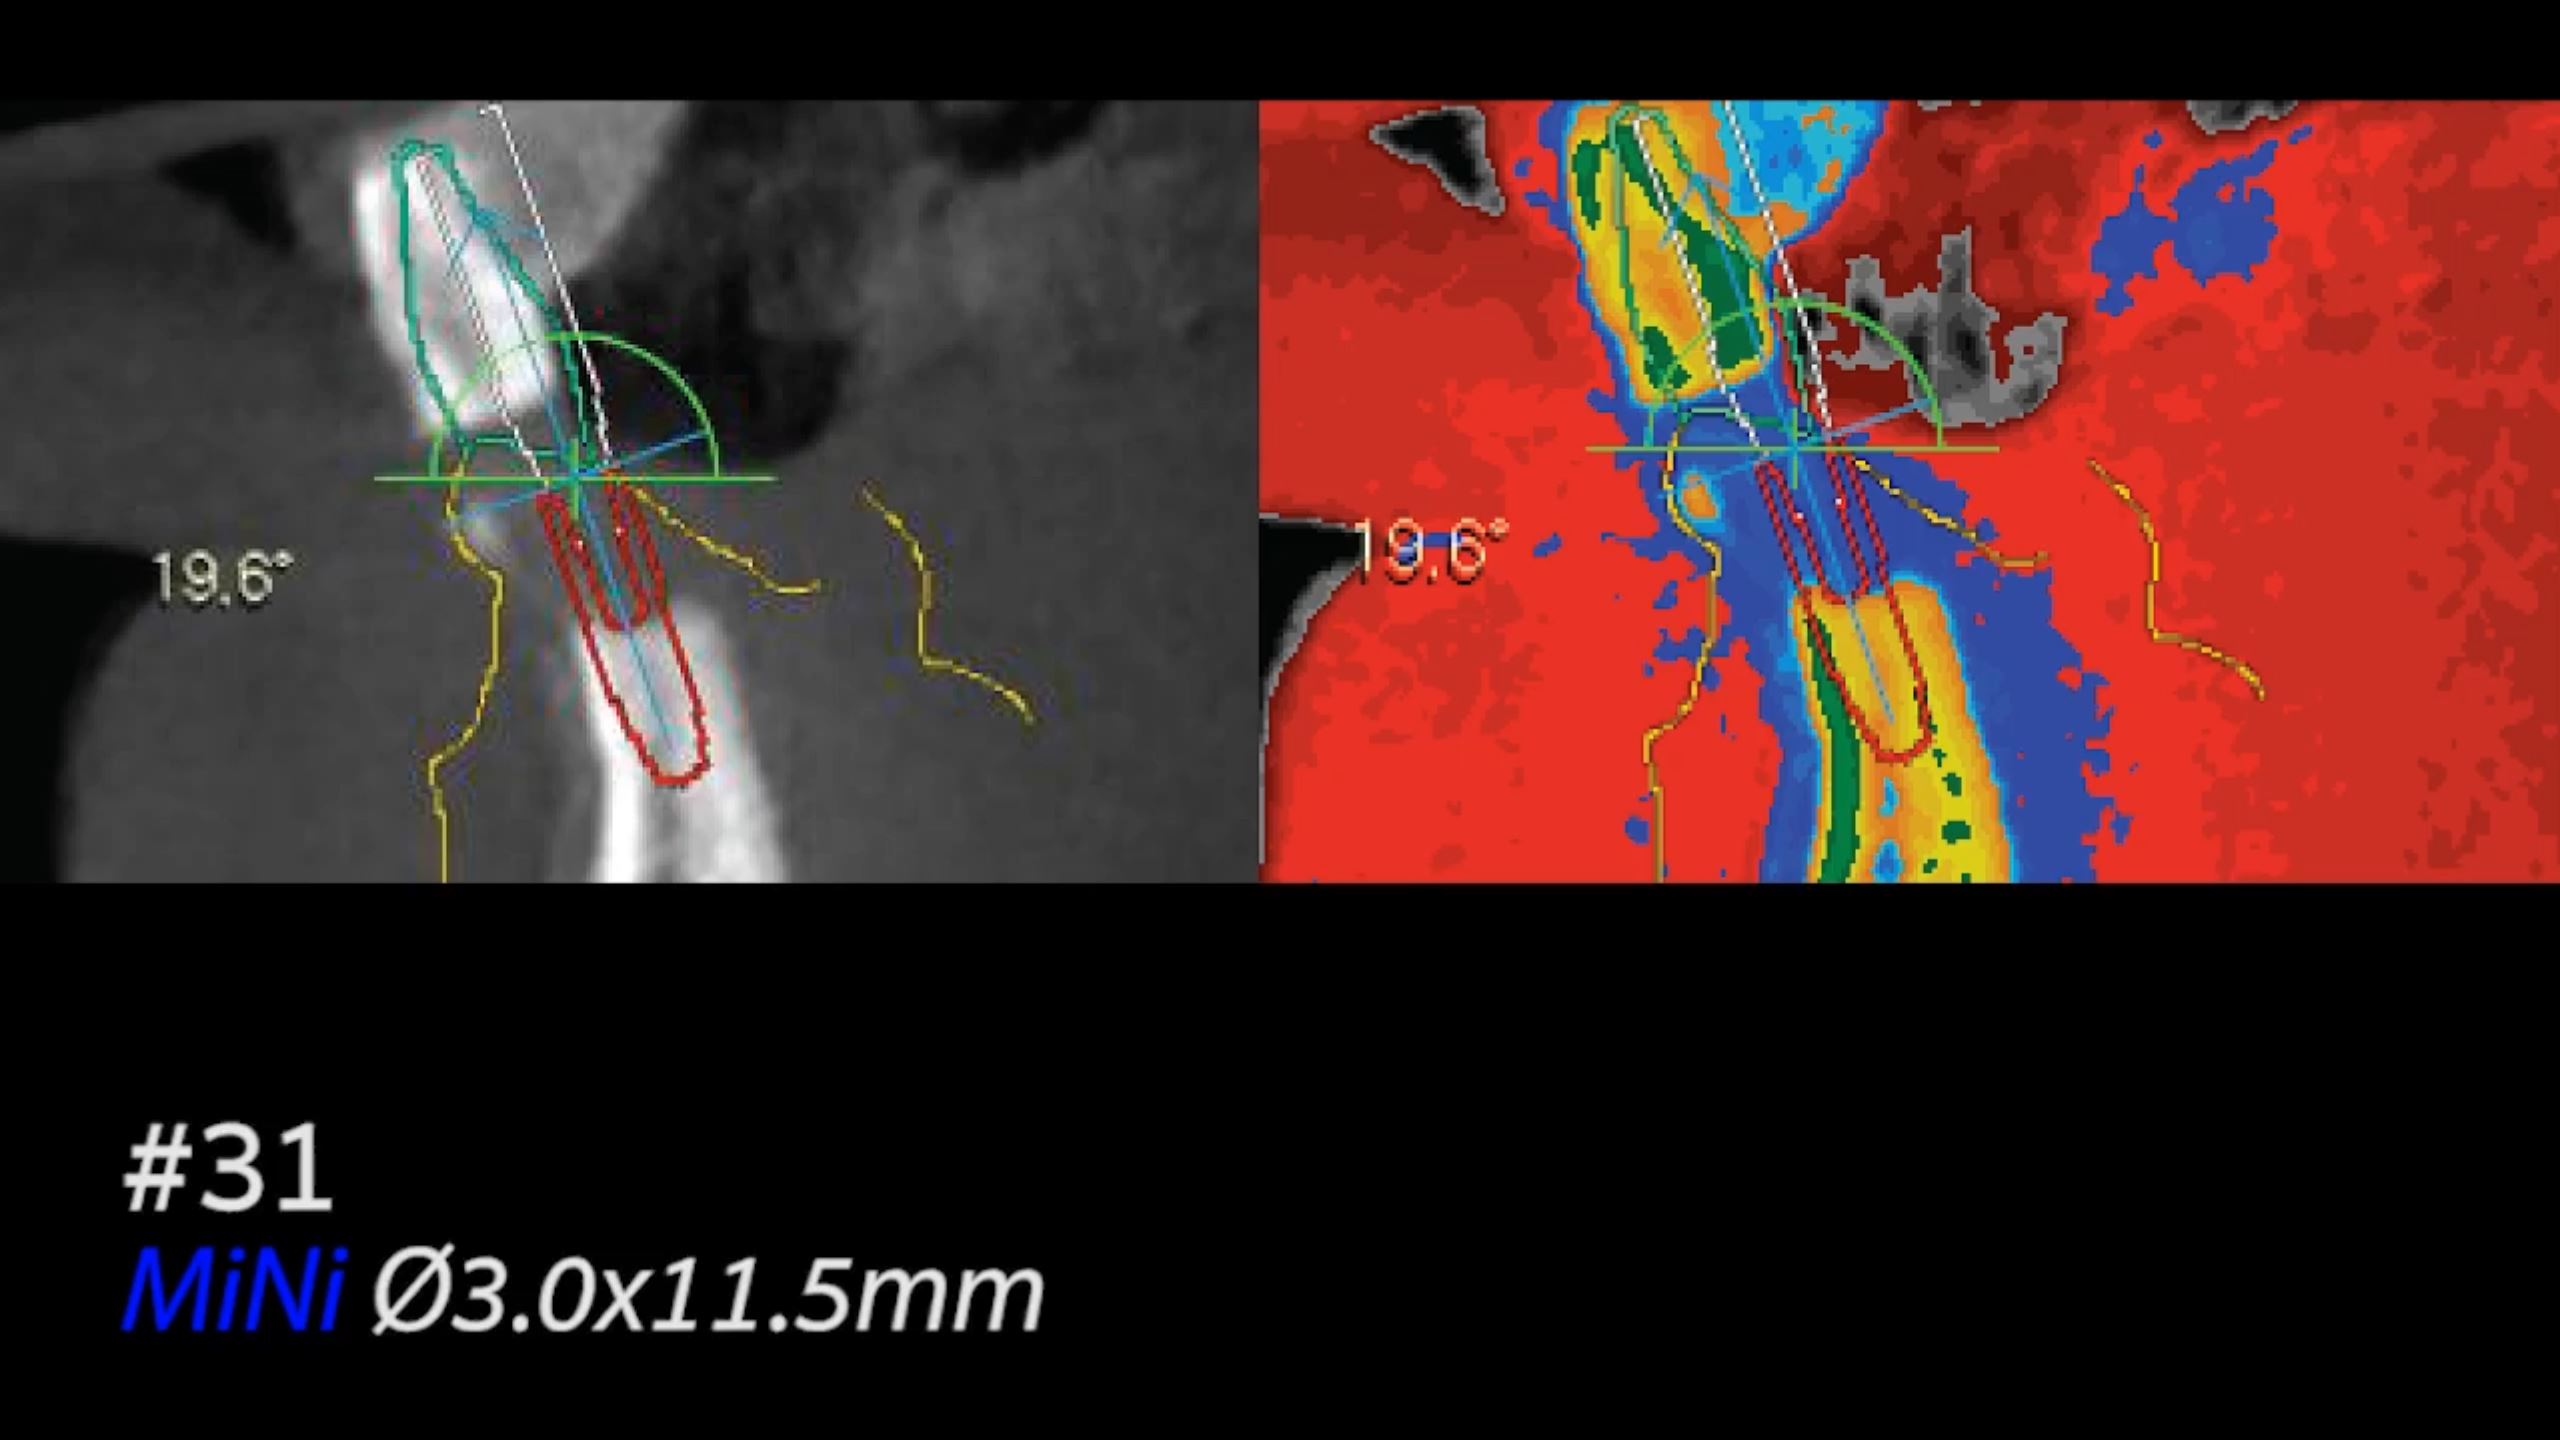

MiNi Clinical Case with Guided Surgery (Live Surgery)

Dr. Jong Cheol Kim,Immediate loading,Digital Guided Surgery,Mandibular Anterior,#31,Guided surgery,Immediate Placement,Flapless,MiNi,R2GATE Guide,MEG-TORQ,MEGA ISQ,Video